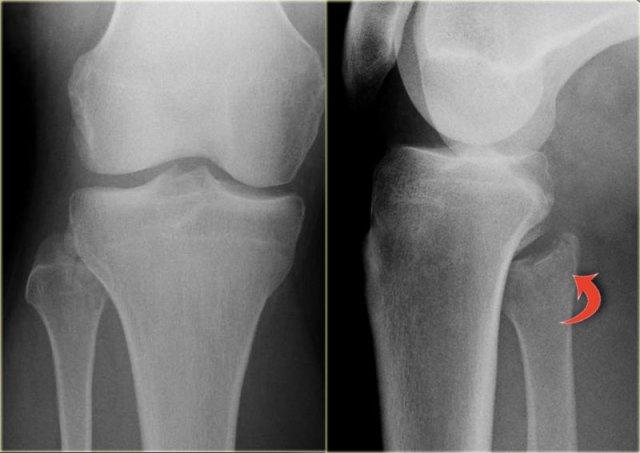

Các hình ảnh cho thấy một trường hợp gãy Weber B rõ ràng.

Trên tư thế thẳng (AP), đường thấu quang dạng tuyến tính là dấu hiệu gợi ý gãy tertius (mũi tên đỏ).

Dấu hiệu này xuất hiện do sự lệch trục nhẹ của mảnh gãy.

Tương tự, trong một số trường hợp, sự lệch trục có thể tạo ra một đường tăng tỷ trọng dạng tuyến tính.

Trong trường hợp này, có gãy Weber B kèm theo bong điểm bám mắt cá trong.

Đường tăng tỷ trọng trên tư thế thẳng (AP) gợi ý một mảnh gãy tertius lớn.

Gãy tertius này cũng có thể thấy trên tư thế nghiêng, nhưng trong nhiều trường hợp chúng ta cần kết hợp thông tin từ cả hai tư thế nghiêng và thẳng để chẩn đoán gãy tertius.